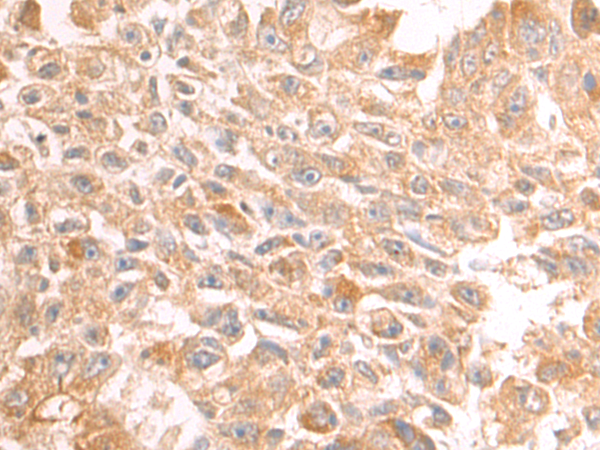

分类: 科研抗体货号: P09865别名: PC-TP; STARD2应用: WB,IHC反应种属: Human, Mouse